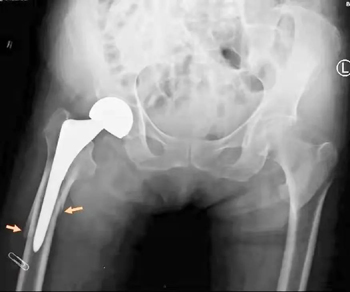

患者是一名81岁高龄女性,因摔伤右侧髋关节到积水潭医院老年创伤骨科住院治疗。特殊的是,患者7年前曾因跌倒后右侧髋部着地,诊断为右侧股骨颈骨折,这种骨折也被称为老年人的“人生最后一次骨折”,骨折后死亡率和致残率很高,老人当时进行了人工股骨头置换术,术后很快康复至正常的生活,7年来行走活动自如。不幸的是,患者这次再次跌倒受伤导致右侧股骨假体周围骨折,比上次更加复杂、治疗也更加困难,手术风险更高。

经过治疗团队术前详细规划,2022年1月12日,团队按照手术设计顺利完成了骨折的复位固定手术,手术用时1小时45分钟,出血量400ml。术后影像显示,骨折解剖复位,定制钢板位置得当,线缆环扎及置钉位置理想,完美实现了术前规划的手术目标。